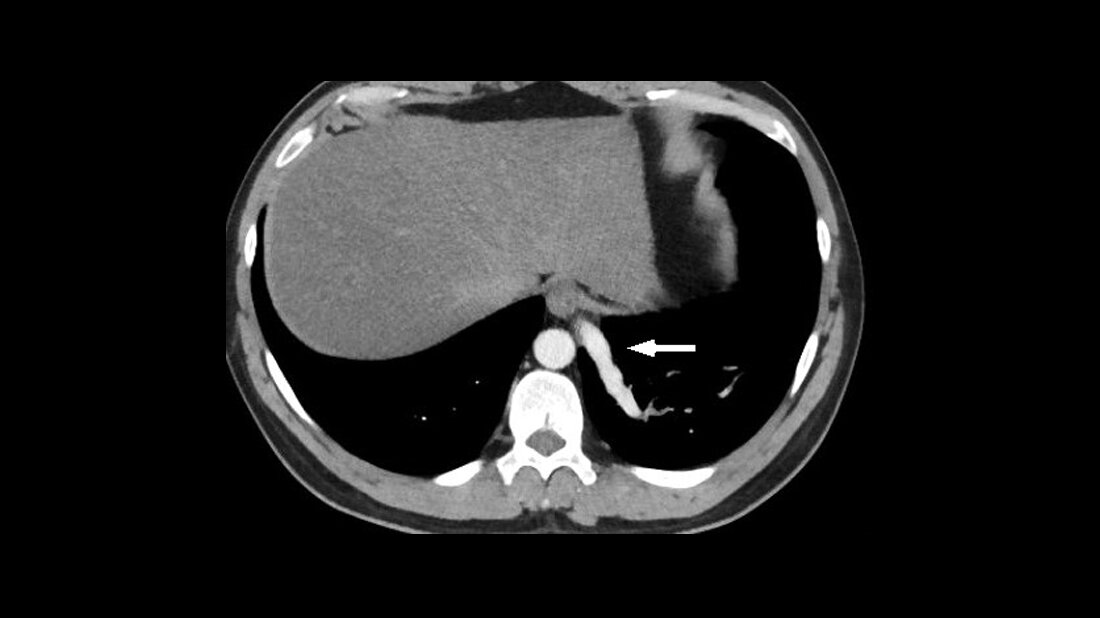

Intrahepatische portosystemische venöse Shunts sind seltene vaskuläre Malformationen. Sie können intra- und extrahepatisch vorkommen, asymptomatisch sein oder verschiedene Symptome aufweisen einschließlich einer Enzephalopathie. Kinder mit hereditärer Teleangiektasie sollten wegen des erhöhten Risikos der Entwicklung vaskulärer Malformationen, vorrangig in der nasalen Mukosa, der Lungen und des Gastrointestinaltrakts, kontrolliert werden.

Intrahepatic portosystemic venous shunts are rare vascular malformations. They may be intra- or extrahepatic, can be asymptomatic or present with various symptoms including encephalopathy. Because of the risk of developing vascular malformations children with hereditary telangiectasia should have regular medical check-ups. The most frequent locations being the nasal mucosa, the lungs and the gastrointestinal tract.